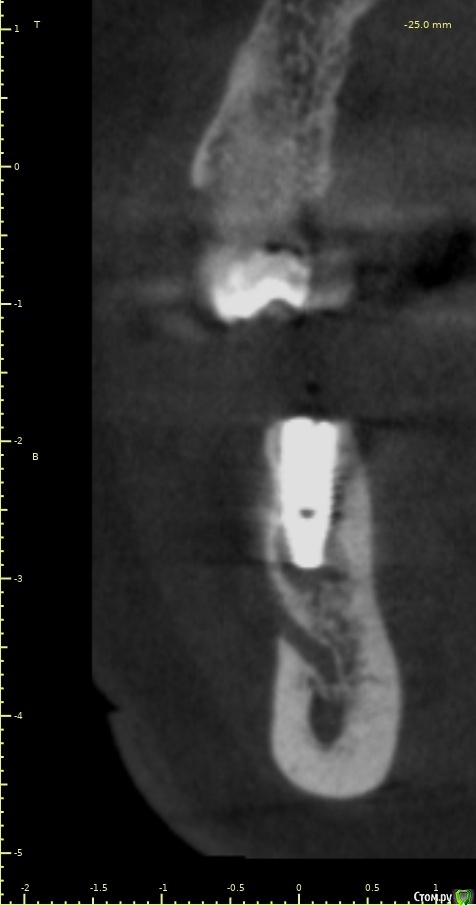

Женька Опубликовано 28 ноября, 2020 Поделиться Опубликовано 28 ноября, 2020 (изменено) Приветствую коллеги. В общем три недели назад 07.11.20 установил пациентке 2 имплантата в позиции 45-46. Гребень по ширине был около 6.5мм в области 4.5 и около 7.2мм в области 4.6 (с учётом заглубления на 1.5-2мм). Это была наверное первая имплантация во время которой я чувствовал себя спокойно и расслабленно. Всё прошло хорошо, немного покопался с непосредственным введением имплантатов, тк никак не хотели топиться на нужные 1.5мм. Поэтому пробовал методику с выкручиванием на пару витков и снова закручиванием. Особого толку не получил, потому взял финальную фрезу и чуть углублял ложе. Так несколько раз, тк боялся всё-таки немного что задену менталис и нлн. Ввиду того, что биотип у пациентки тончайший и язычно было совсем-совсем тонко - заглушки и швы. Назначил нпвс, ванны хг, аб терапию. Но на утро следующего дня пациентка сказала, что чувствует себя шикарно, решили что нпвс оставим, а аб терапию применять не будем (и грешу что в этом мою ошибка).Через неделю сняли швы, всё отлично.Спустя два дня после снятия начались какие-то "костные" боли, как говорит пациентка в области 4.5 импланта. Которые то отпускают, то снова наплывают. На 4.4 есть дефект твердых тканей (на фото виден), но судя по всему беспокоит не он .Пальпация вестибулярно в проекции 4.5 импланта болезненна, небольшая гиперемия, отёка нет. Гигиену пациентка запустила, тк боялась туда залезать и чистить. Снимки прилагаю первые два от 07.11, два последующих 28.11. Ну и внутри ротовые день операции и сегодняшние числа.Похоже 4.5 на выход? своими "туда-сюда" наверняка я нагрел всё что можно... снова расстройство в той работе, где накосячить предельно сложно... Добавка: пить аб ведь сейчас уже бесполезно? Изменено 28 ноября, 2020 пользователем Женька Ссылка на комментарий

Женька Опубликовано 14 декабря, 2020 Автор Поделиться Опубликовано 14 декабря, 2020 (изменено) Наконец-то получил КТ от пациентки...Боли значительно уменьшились, практически не беспокоит... Коллеги, что думаете? Я так понимаю это уже не фон от титана? и вердикт всё-таки один? Сам склоняюсь всё-таки более к понаблюдать. Вестибулярно конечно очень тонко Толщина была ~ 6.7мм Изменено 14 декабря, 2020 пользователем Женька Ссылка на комментарий

Irouil Опубликовано 14 декабря, 2020 Поделиться Опубликовано 14 декабря, 2020 Ну и где тут язычно передавленная кортикалка? Меня смущает только картина в области верхушки симптомного винта, ну и заглубление Я бы дождался уже срока интеграции Ссылка на комментарий

Женька Опубликовано 14 декабря, 2020 Автор Поделиться Опубликовано 14 декабря, 2020 Ну и где тут язычно передавленная кортикалка? Меня смущает только картина в области верхушки симптомного винта, ну и заглублениеНе знаю, я про язычную кортику не говорил. Меня тоже смущает... и в области соседа такого фона (а это не фон я уверен) нет... А с заглублением что не так? по прицелам там 1.5-2мм, на кт почему-то этих мм вообще нет и как будто крестально стоят Ссылка на комментарий